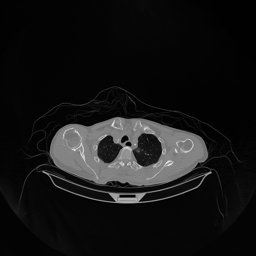

The results for simulated noisy data are shown in Fig. 2. The first and third rows display two representative slices from the test set, and the second and fourth rows present the corresponding error maps. The traditional WCE method suppresses cupping artifacts and recovers some missing anatomical structures but still shows noticeable deviations from the ground truth. Predictions from the four diffusion-based models demonstrate a markedly improved ability to restore anatomical structures. Among them, cDDPM fails to fully reconstruct the patient bed and retains residual noise in its outputs. This noise is attributable to an incomplete reverse denoising process rather than residual Poisson noise, as evidenced in our noise-free experiments (Fig. 5 in the Appendix). PatchDiffusion, diffusionGAN, and I2SB achieve similar visual quality, with I2SB producing the cleanest and most consistent reconstructions.

The experimental results on clinical head data are shown in Fig. 4. The reference images were reconstructed using the fast iterative shrinkage-thresholding algorithm (FISTA) with total variation regularization from non-truncated projection data. In the WCE reconstructions (Fig. 4(b)), severe truncation prevents accurate recovery of anatomical structures outside the FOV. Despite being trained solely on simulated data with a domain gap, all deep learning models can restore a substantial portion of the missing anatomy. Among them, the diffusion-based methods recover soft-tissue boundaries more faithfully than the conventional deep learning approach FBPConvNet, highlighting their stronger image generation capability. However, cDDPM reconstructions exhibit more noticeable noise than those from other methods, consistent with the simulated data results. The patchDiffusion model introduces artifacts within the FOV, likely due to its patch-wise processing strategy. While I2SB shares the same limitations as other diffusion models in perfectly restoring soft-tissue detail, it produces fewer residual noise patterns and fewer artifacts within the FOV boundaries. Overall, Fig. 4 demonstrates the strong efficacy of I2SB in reconstructing real CBCT data.